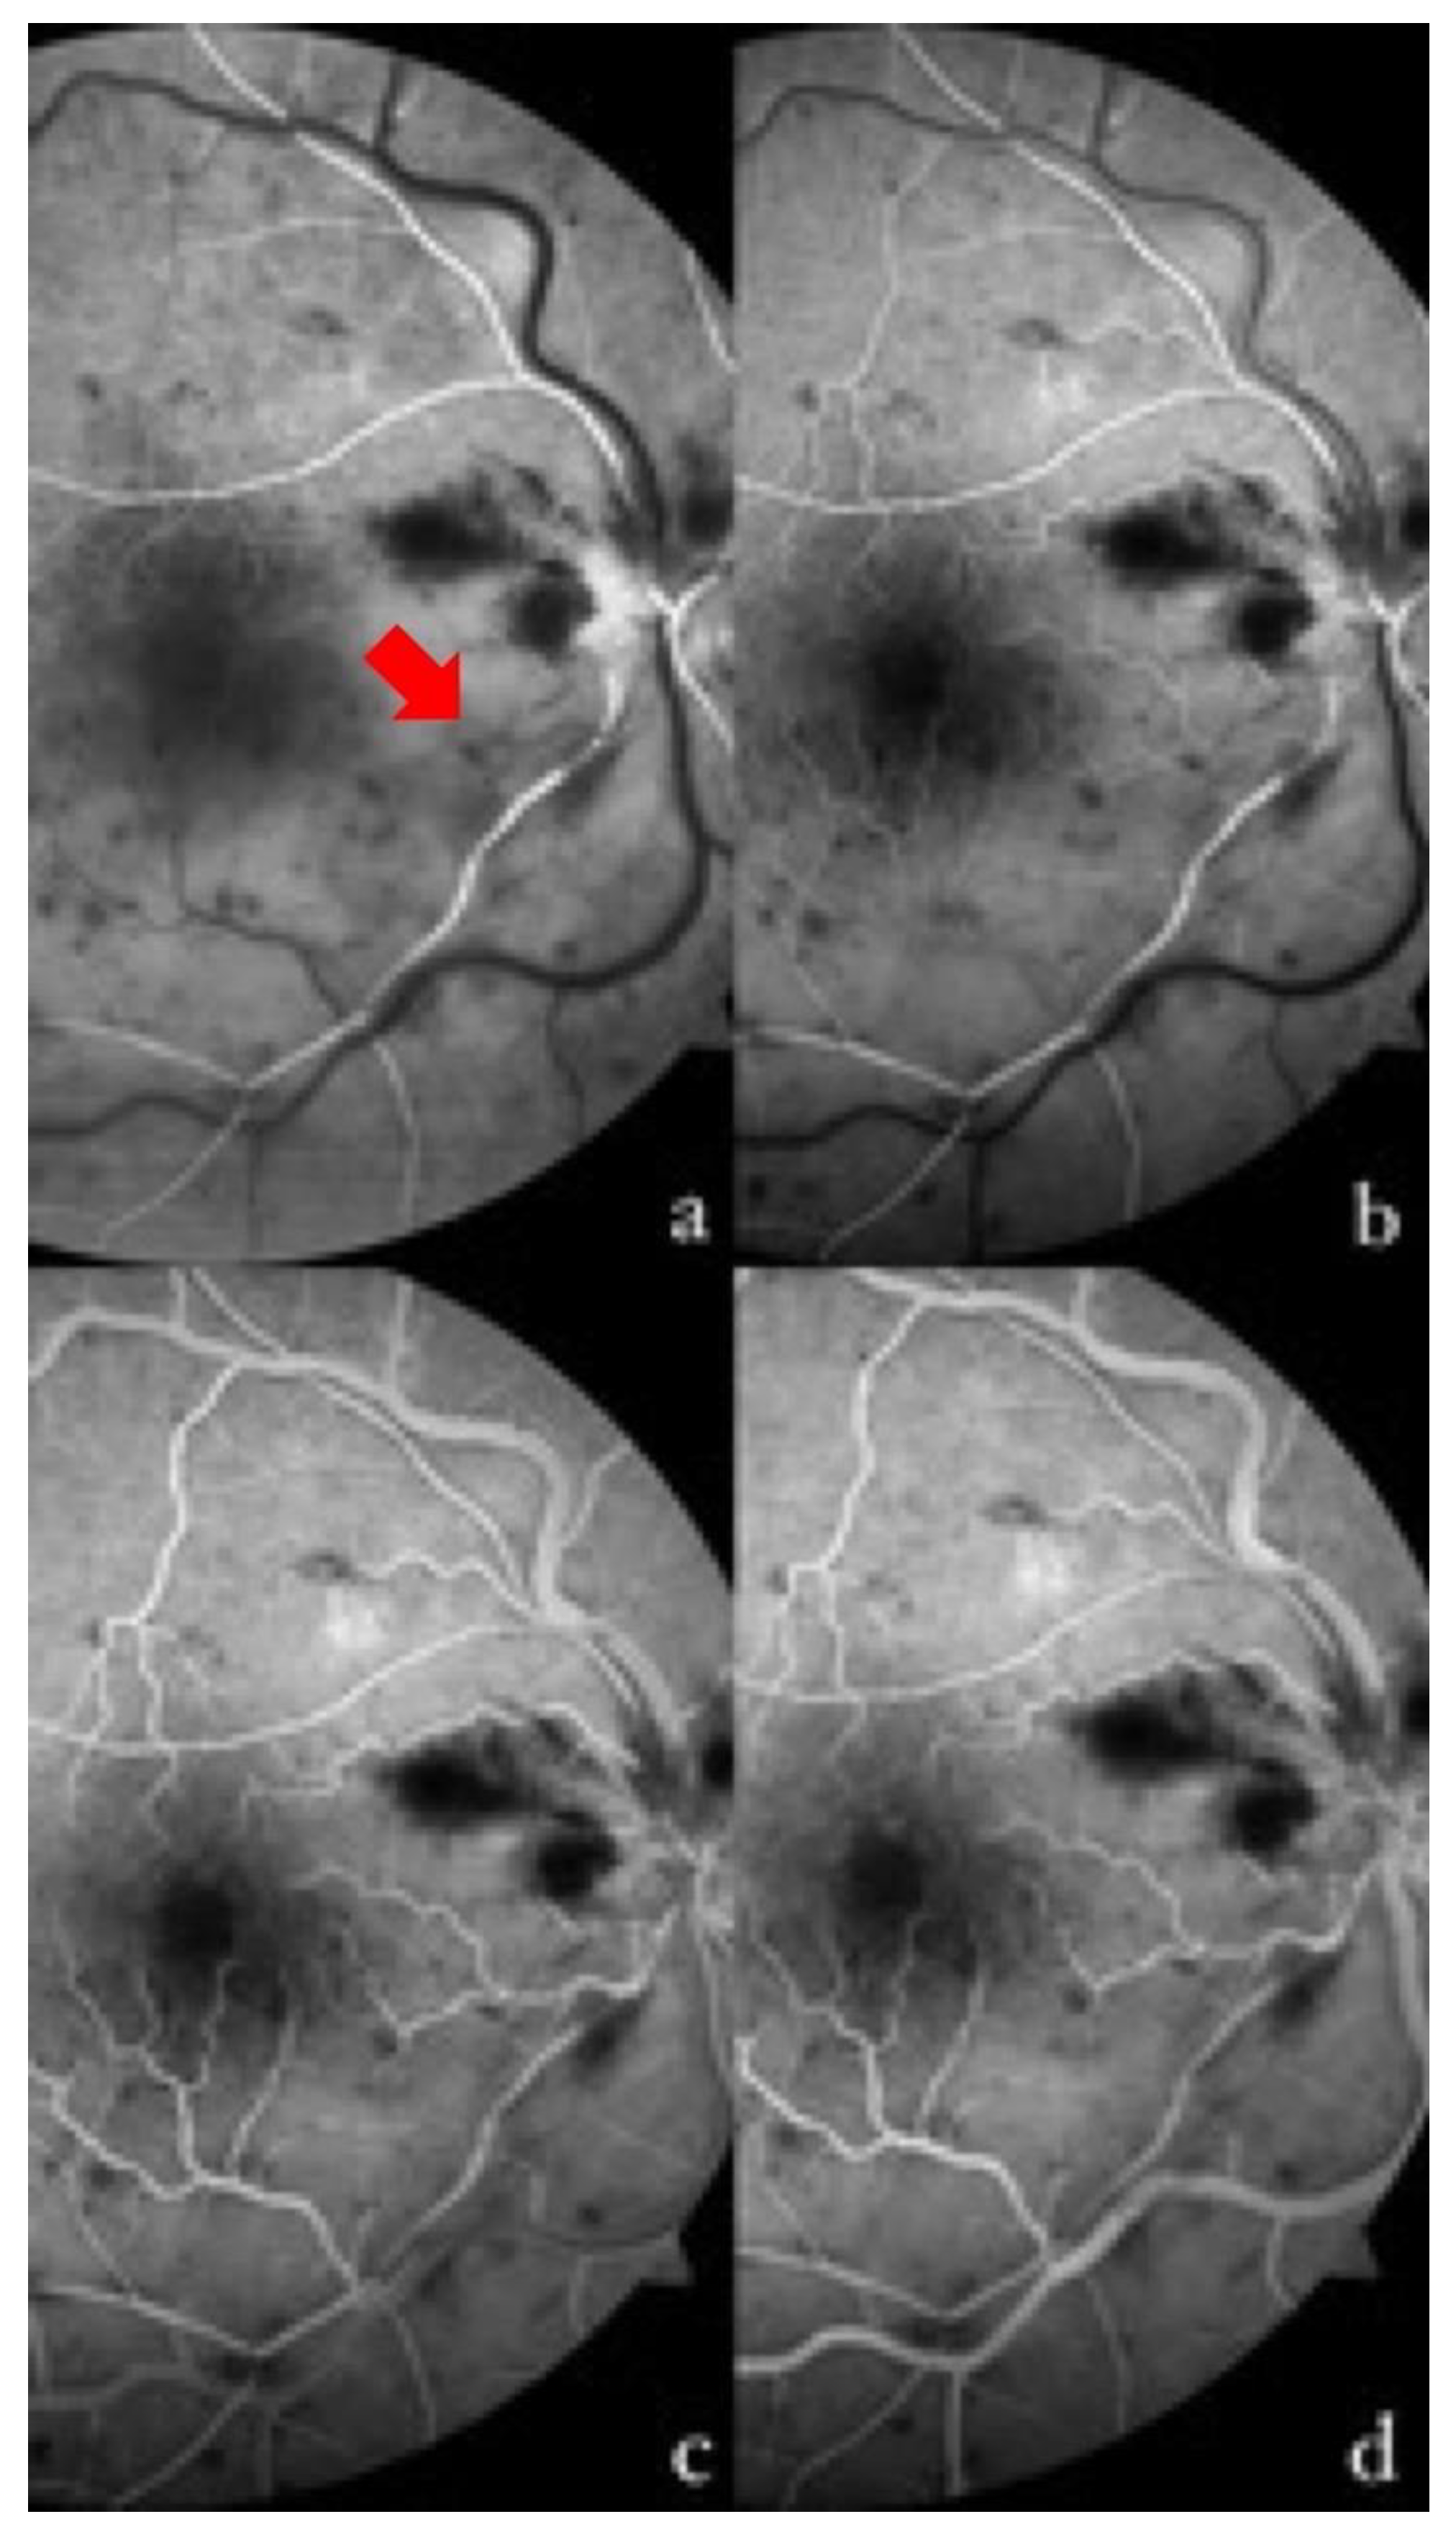

Three days after admission, the BCVA further improved to 20/50, and fluorescein angiography was performed (Visucam 524, version 6.0, Carl Zeiss Meditec, Germany) (Figure 1). The exam confirmed the diagnosis, showing a delayed fluorescence of the infero-temporal arterial branch, with incomplete filling at early and late times and sparing of the other arterial branches, delayed venous filling over the entire retinal field, greater in the inferior sectors, and the cattle-trucking sign of infero-temporal peripheral arterioles. Furthermore, the fluorescein angiography revealed an early hypofluorescence for superficial and deep retinal hemorrhages throughout the evaluated retina (mask effect), with areas of capillary nonperfusion (vascular dropout) in the inferior sectors and venous pruning, a fovea avascular zone size increase in the inferior sectors due to the presence of areas of nonperfusion, and the absence of late macular leakage.

Figure 1. Fluorescein angiography of the right eye at different times in the examination. (a) At 13 s, the complete filling of the supero-temporal arterial branch is shown, with the incomplete and delayed filling of the infero-temporal branch and some segments (red arrow). (b) At 16 s, the presence of a capillary network at the posterior pole in the superior sector, and its absence in the inferior sector, is well shown. The initial laminar filling of the superior veins, and a slight delay in the temporal inferior one, can be observed. There is a progressive venous filling that completes at 22 s (c) in the upper sectors, and at 36 s (d) in the lower sectors. Non-perfused arteries and areas can be seen in the affected retina on the temporal inferior side.